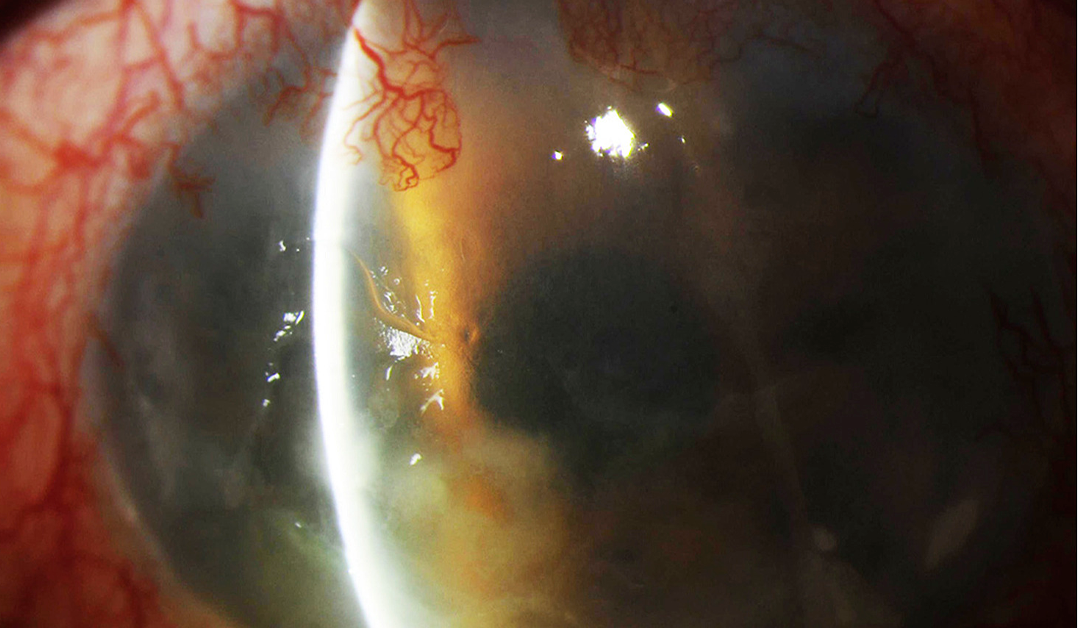

Disfunción de glándulas de Meibomio: pasado o presente

Dice el viejo adagio de los abuelos: “todo tiempo pasado fue mejor”, en muchos casos tienen razón, pero en cuanto a la Disfunción de Glándulas de Meibomio (DGM) la situación debería ser diferente. En el promedio de atención de este tipo de pacientes, el tratamiento...